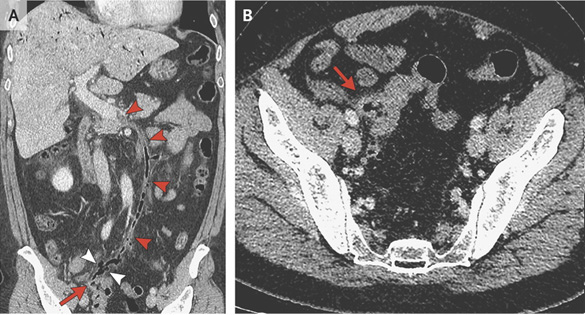

小腸憩室炎 嘉義長庚一般外科

大腸憩室炎 嘉義長庚一般外科